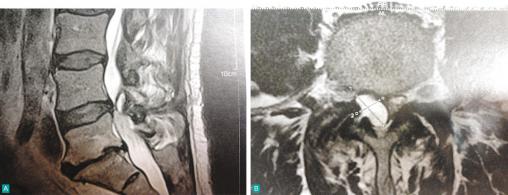

Très gros kyste articulaire postérieur responsable d'une sciatique L5 droite

T2, coupe sagittale (A) et axiale (B).